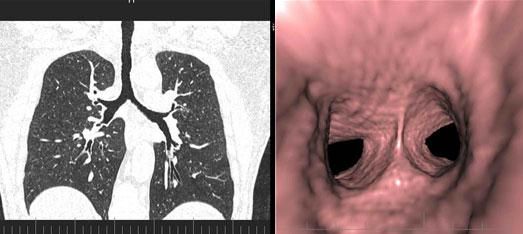

三、先進的仿真内鏡技術:

從多角度,多平面分析空腔髒器病變,可應用于胃、結腸、血管、氣管支氣管、膽道等仿真内鏡檢查,大大提高了病變的檢出率和診斷的準确性。

3、肺動脈血管成像: